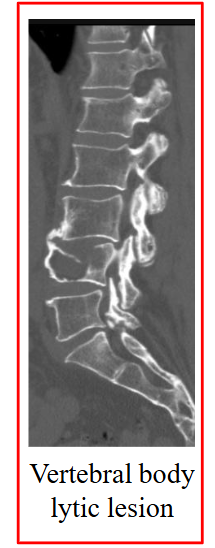

Bone Imaging Methods

CT Skeletal survey:

- CT of skull, long bones & axial skeleton

- Detects "lytic lesions" (local loss of bone)

- Size of local lesion

Skeletal Survey: Lytic Bone Lesions

Skeletal survey includes:

- Lateral skull

- Frontal chest film

- Cervical-thoracolumbar spine

- Shoulders

- Pelvis, femur

.

Majority of lesions are sharply defined and lytic